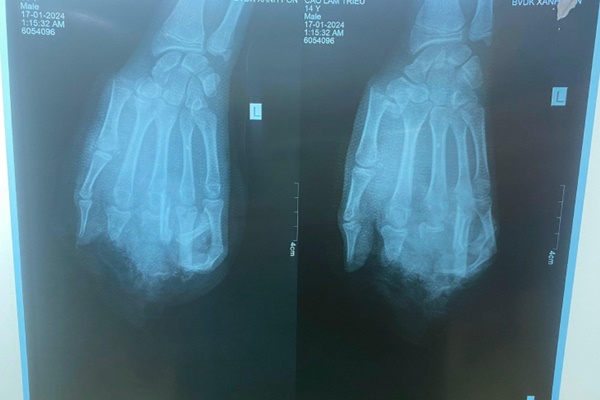

Bệnh nhận C.T.L (14 tuổi, trú tại Hải Dương) được gia đình đưa vào Bệnh viện Đa khoa Xanh Pôn (Hà Nội) cấp cứu trong tình trạng tình trạng dập nát bàn tay trái, gãy xương bàn ngón I, đầu ngón I, V còn hồng.

Hình ảnh phim chụp X-quang của bệnh nhân. Ảnh: BVCC.